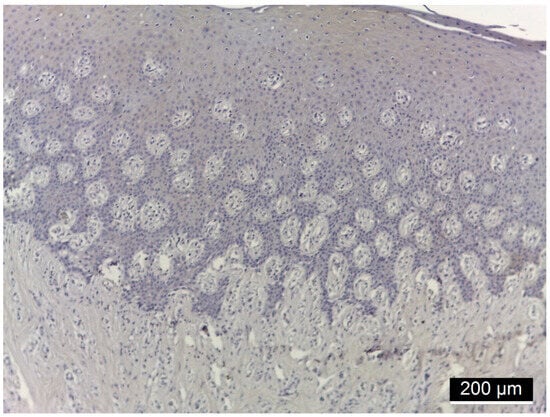

| Patients Number | Diagnostic | Immunoreactivity Intensity MMP-14 | ||

|---|---|---|---|---|

| Membranous | Cytoplasmatic | Nuclear | ||

| 9 | Diabetes mellitus + Periodontitis | + | − | − |

| 7 | Diabetes mellitus + Periodontitis | +++ | − | − |

| 10 | Periodontitis (control) | + | − | − |

| 7 | Periodontitis (control) | − | − | − |

| Location | IR Intensity | DM + PD n = 16 | PD n = 17 | Chi Square Test p |

| MMP-14 | ||||

| Membranous | (−) (+) (++) (+++) | 9 (56.2%) 7 (43.8%) | 7 (41.2%) 10 (58.8%) | 0.004 0.883 nc 0.002 |

| Cytoplasmic | (−) (+) (++) (+++) | 16 (100%) | 17 (100%) | 1.000 nc nc nc |

| Nuclear | (−) (+) (++) (+++) | 16 (100%) | 17 (100%) | 1.000 nc nc nc |